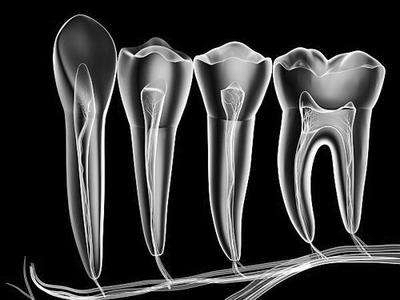

牙髓具有4种基本功能:1、成牙本质细胞形成牙本质;2、血液系统向牙髓牙本质复合体提供营养成分;3、感觉神经纤维传导痛觉;4、成牙本质细胞及结缔组织成分对外界刺激的保护性反应。

牙髓在其整个生命过程中有不断形成牙本质的功能,但形成牙本质的速率和形式有所不同。在牙萌出之前所形成的牙本质为原发牙本质,它呈管状且排列有规律,其原因是成牙本质细胞的排列不拥挤,牙也还未开始行使功能。在牙萌出之后所形成的牙本质为继发性牙本质,它也是规则的管状牙本质,且牙本质小管与原发性牙本质中的小管相延续。随着成牙本质细胞分泌基质和逐渐后退,它们就会变得拥挤且排列紊乱,所形成的继发性牙本质呈波纹状,且形成的速度也相对缓慢。

牙髓受到外界异常刺激如龋病、磨损、酸蚀症和备洞等所诱发形成的牙本质称为第三期牙本质,它是一种防御机制,其目的是保护牙髓免受不良刺激。第三期牙本质以往也被称为修复性牙本质、刺激性牙本质或不规则牙本质等。目前认为,若第三期牙本质由原来的成牙本质细胞形成,则称为反应性牙本质,虽然牙本质形成的速度较快,但牙本质小管与继发性牙本质中的小管相延续。若第三期牙本质由新分化的牙本质细胞样细胞形成,则称为修复性牙本质,其牙本质小管形态不规则,数目较少甚至缺乏,也不与继发性牙本质中的小管相延续。若修复性牙本质的形成速度过快,基质中就会含有细胞或组织,形成类似骨组织样外观,因此又被称为骨样牙本质。